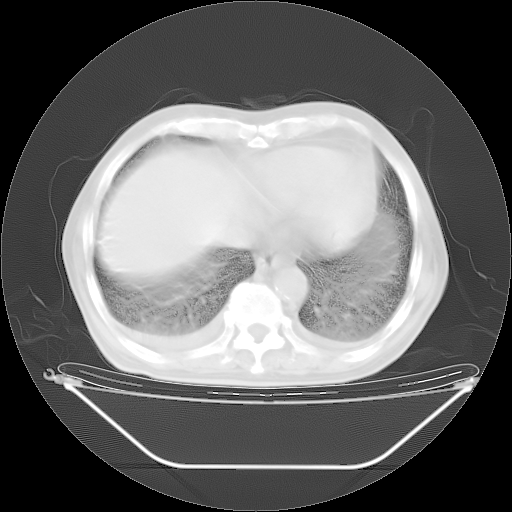

5月9日肺部CT(在4月27日齐鲁医院肺部CT描述部分肺组织磨玻璃样改变,12天后肺组织广泛磨玻璃样改变)

2009年5月9日肺部CT

大致读了系列胸部CT:纵隔窗无明显异常,肺窗:从4、27至今:主要是双肺中下野外带可见毛玻璃样改变,目前处于急性肺泡炎阶段,至于原因考虑1、结替组织或胶原血管性疾病所致?2、恶性疾病如恶组在肺部所致的表现或细支气管肺泡癌?3、药物或其它原因如肺蛋白沉着症所致肺泡炎目前不太可能?总之,明天就去请我院的呼吸科、感染科、血液科和临免专家会诊哈。